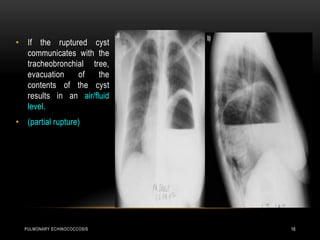

• If the ruptured cyst

communicates with the

tracheobronchial tree,

evacuation of the

contents of the cyst

results in an air/fluid

level.

• (partial rupture)